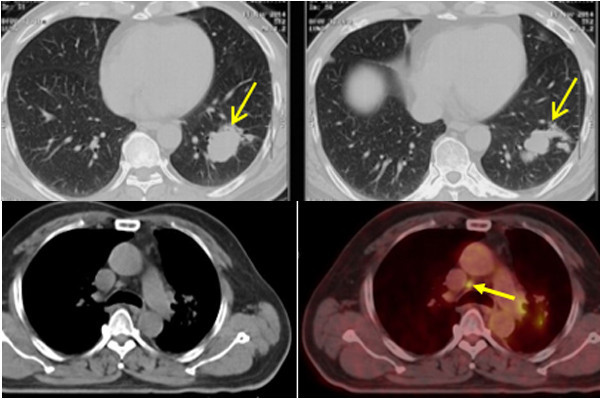

Mọi thứ vẫn diễn biến tốt cho đến năm thứ 4 (2018), khi kiểm tra PET/CT để đánh giá tổng quát, bác sĩ lại phát hiện phổi trái tái phát khối u, kích thước 4,6×1,9 cm, lan sang phổi phải và di căn lên hạch thượng đòn, hạch trước. Bệnh nhân tiếp tục được điều trị duy trì bằng hoá chất dạng uống.

Hình ảnh khối u ở phổi bệnh nhân V. (2 ảnh trên) và hình ảnh khối u thu nhỏ sau điều trị